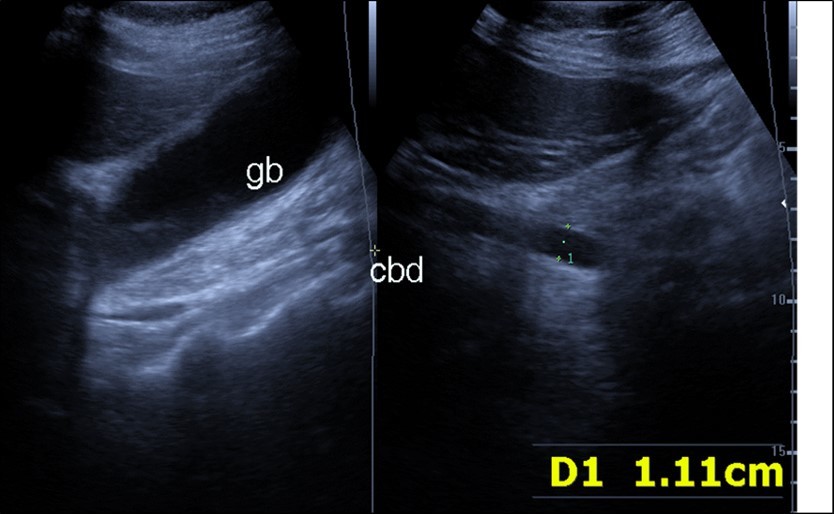

Abdominal ultrasound may revealed any of the followings:-Mild hepatomegaly with echogenic parenchyma and ascites in cases with hepatic impairment (Figure 4, Figure 5) ,thick walls of gall bladder with mildly dilated Common bile duct suggesting of biliary stasis and cholecystitis (Figure 6) .Abnormal renal echogenicity (Figure 7), suprarenal gland enlargements with heterogeneous texture ,splenic wedge shape area of hypoechogenicity ,thickened walls of bowel mainly the rectosigmoid region ,dilated bowel loops with free peritoneal fluid, and gases in the bowel wall with mesenteric and portal vein gases suggesting of bowel wall infarction13.

Figure 4.Real time ultrasound showing thickened wall of gall bladder (gb) with dilated Common bile duct (cbd) in patient with severe Covid-19.